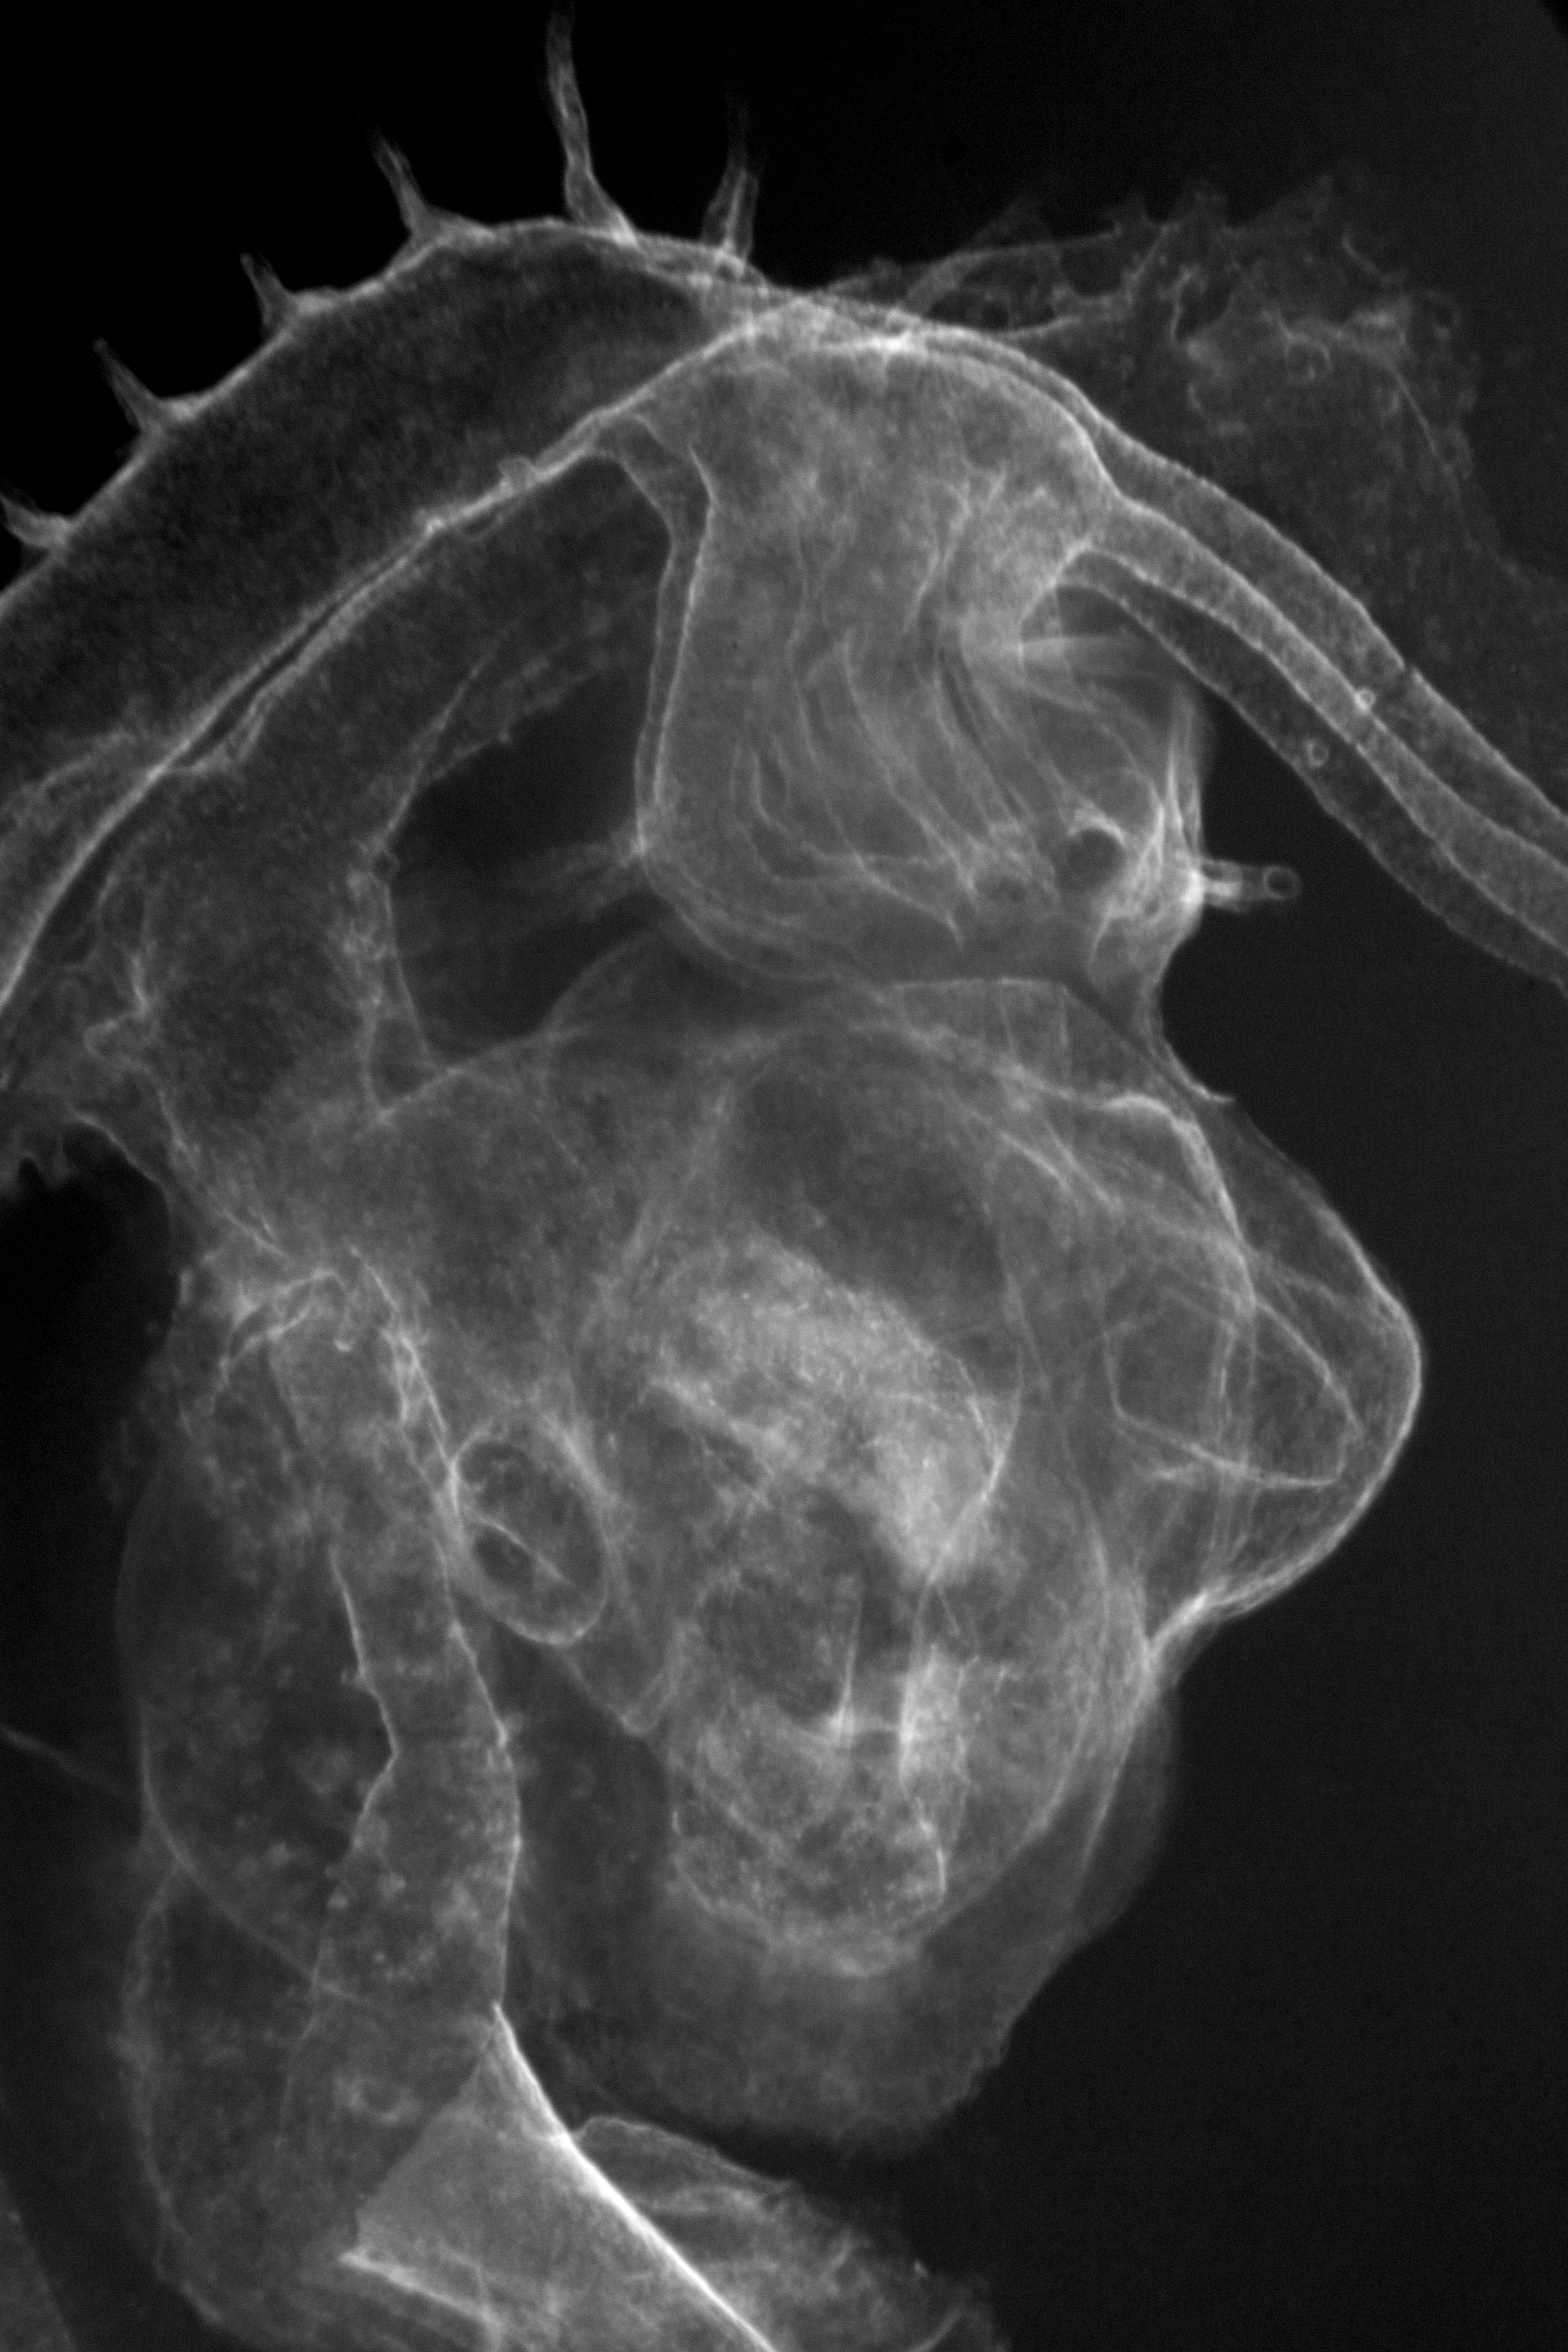

Chick Embryo Microangiography

Hamburger-Hamilton (HH) Stage 22 (approx. 4 days)

X-Ray Micrographs